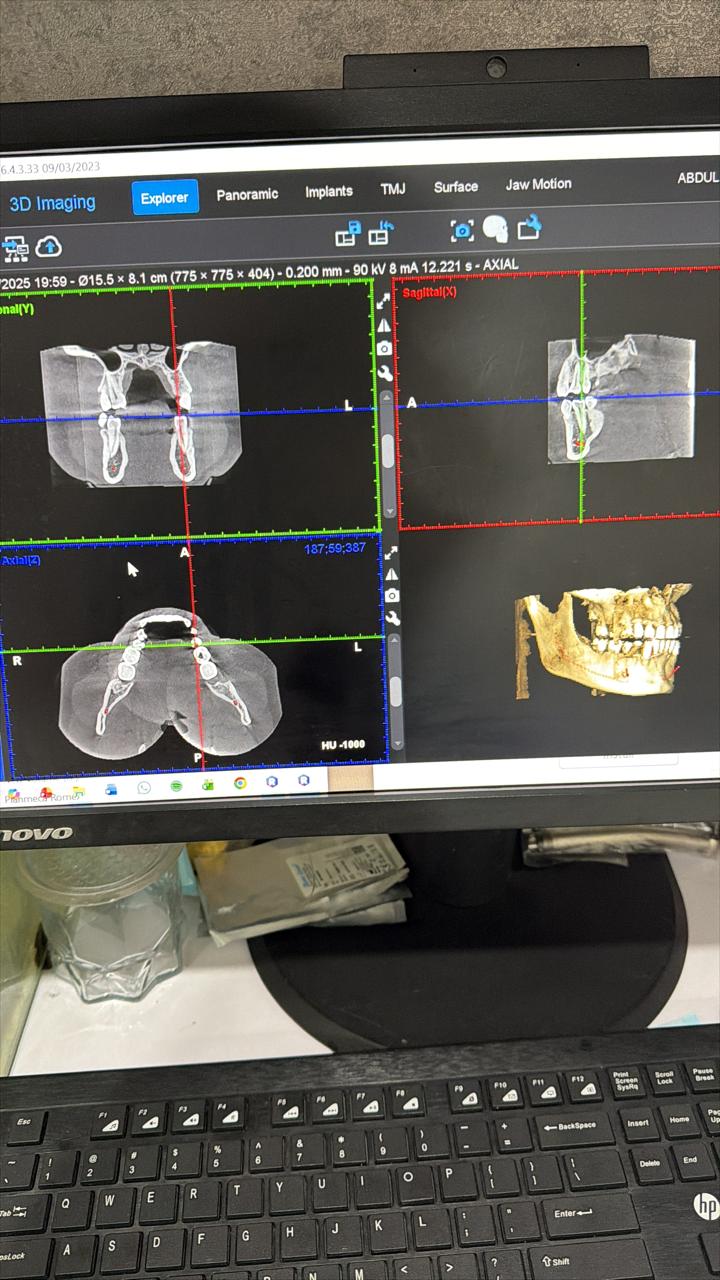

Case evaluation with CBCT for precise diagnosis and optimal treatment outcomes.

Case evaluation with CBCT for precise diagnosis and optimal treatment outcomes.